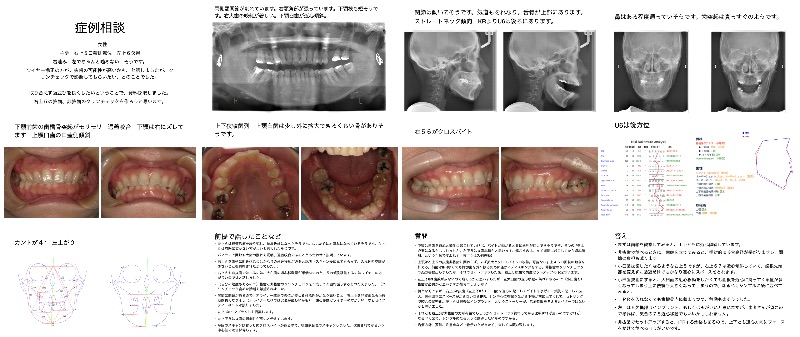

- Qクリンチェックの修正バイトウィング

S様 下顎後退のケースの方で、今までアーチと叢生を整えてきました。ここからバイトウイングにより、顎位を前方に誘導したい計画です。

動かし方に無理がないか見ていただけますでしょうか

IPRは返ってきたクリンチェックのままにしているのですが、ここまで必要でしょうか?

宜しくお願いします。 - A正規会員もしくはQAアクセス会員になると、Aが表示されます。